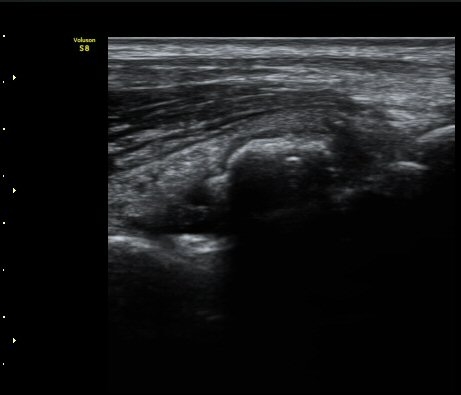

ÃÊÀ½ÆÄ °Ë»ç